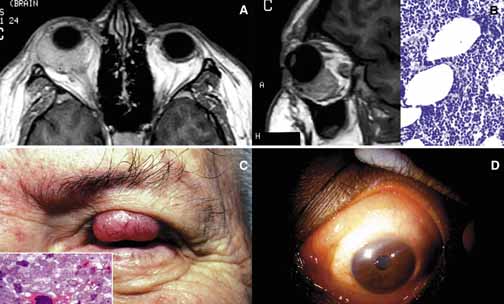

ANOPHTHALMOS/MICROPHTHALMOS When the globe is abnormally developed, microphthalmos, congenital cystic eye, and extremely rarely, anophthalmos occur. Microphthalmos usually occurs as a unilateral condition and in approximately 10% of cases it is associated with other craniofacial malformations including agenesis of the corpus callosum, polymicrogyria, and mid-line arachnoidal cysts. Microphthalmos may be seen as a part of several genetically determined neuronal migration disorders such as Walker-Warburg syndrome, Aicardi syndrome, and Fukuyama congential muscular dystrophy.9,10 In cases of microphthalmos and anophthalmos the orbit may be well formed but does not develop to a full adult volume. The mechanism by which the presence of the globe effects the growth of the orbit is not well understood. Microphthalmos may be associated with a colobomatous cyst as a result of the abnormal closure of the embryonic optic fissure leading to the prolapse of neuroectodermal tissues into the orbit (Fig. 1) This cystic structure may increase rapidly in size to overshadow the abnormal globe and may be confused with a neoplasm. When cystic lesions in the orbit are suspected imaging studies should be performed not only to look for other intracranial abnormalities but also to establish the possible connection of the cyst to the colobomatous globe versus to abnormally formed meninges.11 Macrophthalmos (buphthalmos) may also rarely develop as a congenital anomaly in patients with Sturge-Weber syndrome and rarely in neurofibromatosis type I. ORBITO-CRANIAL MALDEVELOPMENTS Cephalocele results from the extension of maldeveloped CNS tissues including meninges (meningocele), brain parenchyma (encephalocele), and the combination of the two (meningoencephalocele) into the orbital cavity.12,13 Intraorbital cephaloceles may develop anteriorly at the suture lines of orbital bones or posteriorly extending into the orbit from orbital fissures and the optic canal. Depending on the combination of these herniations they contain brain and/or meningeal tissues (Fig. 1). Aberrant fibroglial tissue has also been described in the orbit.14 Hamartoma is a tumor-like proliferation of tissues that normally exist at a given body location. The best examples of orbital hamartomas are the vascular hamartomatous lesions that are composed of vascular elements including capillary endothelial cells, distended or collapsed cavernous blood and lymph vessels, tortuous arterial and venous channels with or without anastomoses, etc. Other examples of hamartomatous orbital tumors include neurofibroma and lipomatous hamartoma.15 Choristoma, however, is a tumor-like proliferation of tissues that are not normally present at a given body location. The most commonly encountered example of orbital choristoma is a dermoid.16 Dermoids that present with many varieties result from the entrapment of epithelial structures at the site of closure of fetal fissures. Superficial dermoid cysts occur primarily subcutaneously anterior to orbital septum or within the anterior orbit. If the cyst wall is made of epidermis without dermal tissues, it is classified as an epidermoid cyst. These lesions are occasionally lined by conjunctival or pseudostratified respiratory epithelium.17 The superficial lesions must be distinguished from deep orbital dermoids that are usually rounded, encapsulated tumors filled with fatty materials, keratin, and dermal structures such as hair particles. Histopathologically the dermoid wall is lined by keratizing squamous epithelium with dermal appendices including hair follicles and sebaceous and eccrine glands.18 Most of the dermoids are well outlined by ultrasonography because of their anterior location thus making CT or MRI rarely necessary.19 If the dermoid is unusually large or located at the frontal zygomatic suture, CT is necessary to document the relationship of the lesion to the bone before surgical intervention. Rarely, dermoids at the fronto-zygomatic suture may develop dumbbell-shaped lesions partially within the orbit and partially extending into the temporal fossa.20,21 Unusually large superior orbital dermoids particularly those that leak and create granulomatous reaction within adjacent soft tissues may erode the bone and extend into the frontal sinus or the cranium (Fig. 2). ORBITAL TERATOMA Teratoma is a germ-cell tumor that contains tissues derived from endoderm, ectoderm, and mesoderm22 (Fig. 1). Therefore, these lesions may contain skin, bowel, lung, brain, thyroid, cartilage, and bone tissues. Most teratomas develop unilaterally and in girls. A majority of these congenital tumors are benign. Occasional reports have documented malignant transformation within orbitocranial teratomas.23 However, these benign tumors continue to grow after birth because of the collection of secretions from different tissues into the partially cystic spaces of the tumor. Some teratomas create massive proptosis and most can only be treated by exenteration. However, some of these lesions have recently been reported to be removed surgically with preservation of the globe and other vital orbital structures. TRAUMA Mechanical Injury Orbital injuries result from the absorption of kinetic energy that occurs whenever the orbital tissues contact an object moving at a different speed.25 The orbital rim is capable of absorbing a considerable amount of kinetic energy without being fractured. Yet, a variety of impact forces striking the orbit may result in fractures in different areas.26 The absorption of the kinetic energy by an orbital bone may lead to contusion and/or laceration of the skin and superficial soft tissues, local deformation of the adjacent structures, globe, orbital soft tissues and bones and increases pressure in the orbital cavity. A common end result of an orbital impact is the fracture of the floor and/or the medial wall (lamina papyracea)27 (Fig. 3). Fractures of other orbital bones occur less often. Foreign bodies may be introduced into the orbit at the time of injury and may cause secondary problems depending on the nature and the location of the foreign body.28 Some foreign bodies such as copper may cause tissue necrosis and degeneration (chalcosis), and others particularly organic matter, may carry organisms such as bacteria and fungi into the orbital tissues and cause secondary infections29 (Fig. 3). Once the fracture of an orbital bone occurs, it may produce sharp edges to lacerate adjacent soft tissue structures including the globe, optic nerve, other nerves, muscles, and vessels.30 Depending on the damage of the particular tissue, functional deficit results. Another issue to deal with in an injured orbit is the development of hematoma, hematic cyst, and cholesteotoma. Hemorrhage in the orbit may occur spontaneously without any physical exertion in healthy individuals. Although terminology is not very strict, hematoma usually refers to a localized collection of blood within orbital soft tissues that develops secondary to trauma. When the blood collection within the orbit becomes organized and surrounded by a thin pseudocapsule, it is known as a hematic cyst31 (Fig. 4). If the hemorrhage develops within an existing lymphatic or vascular tumor, these lesions are known as blood cysts or “chocolate” cysts.32 Hematic cyst consists of a localized collection of blood surrounded by a nonepithelium-lined thin fibrous capsule.33 These lesions usually develop within 1 to 2 weeks of orbital trauma but chronic cases may occur up to 20 years after orbital injury.34,35 They may reach to a size causing proptosis, extraocular motility disturbance, compression on the globe and optic nerve, that can easily be detected with ultrasonography, CT, or MRI. Hematic cysts may develop within the muscle cone or in the extraconal orbital locations.33–36 These cysts are lined by fibrovascular tissue at the periphery and contain degenerated erythrocytes, protein debris, and cholesterol crystals. In many instances the thin nonepithelial lining is adherent to the adjacent structures with fibrous tissue. Cholesteatoma is another cystic lesion that is confined within a “pseudowall” without an epithelial lining.37 Cholesteotomas are usually located in the superior lateral orbit within the lacrimal gland fossa. Imaging studies may show a cystic, semi-cystic, or a solid lesion within the diploe of the bone or within the orbital soft tissues, with or without erosion of the adjacent bone.38 Histopathologically the lesion is composed of cholesterol clefts, hemosiderin, and hematoidin granules, other blood breakdown products and fibrin surrounded by a mixed lymphohistiocytic infiltrate and multinucleated foreign body giant cells.39 On imaging studies these lesions appear as unilocular rounded masses with destruction of the adjacent frontal and zygomatic bones. Although bone involvement in general implies malignancy, the sclerosing character of the bony destruction in choleosteoma, which is best seen in bone window images, favors a benign lesion. Although bone destruction also makes one think along the lines of metastatic tumors, one should also consider benign lesions such as brown tumor, aneurysmal bone cyst, and ruptured dermoid. Multiple cuts of the frontal bone should be examined to rule out the possibility of intracranial extension. Osteomyelitis of the orbital bones evolving as a complication of paranasal sinusitis is another entity that should be considered in the differential diagnosis of cholesteotoma. In osteomyelitis the bone infection extends into the periosteal space and beyond. Precise delineation of the lesion can be performed with CT and MRI particularly in combination with bone SPECT, a sensitive technique used to detect osteomyelitis within cranial and orbital bones.40 Mucocele Although a commonly encountered space occupying lesion in the orbit, mucocele is technically not a neoplasm. It is a cystic cavity lined by pseudostratified respiratory epithelium prolapsing into the orbit from a paranasal sinus, most commonly the frontal followed by the ethmoidal sinus (Fig. 5). Primary mucoceles develop as a result of an inflammatory obstruction of the ostium of the paranasal sinuses. Secondary mucoceles, however, are most commonly seen after orbital trauma and surgery; they may also develop secondary to neoplasms of paranasal sinuses and nasopharynx. If there is a superimposed infection, the lesion is referred to as pyocele. The mucocele develops as a well delineated cystic structure originating from a paranasal sinus. Depending on the location, it may compress orbital structures including extraocular muscles, optic nerve, and the globe.41 Clinical presentation of the mucocele is usually with globe displacement and/or proptosis, extraocular motility deficiency, particularly in the direction of the sinus extension into the orbit, and other compressive symptoms.42 The crepitant or calcified hard wall of the mucocele may be palpated underneath the superior or medial orbital rim. Mucoceles in general, are rare in children, however, a unique variant, ethmoidal mucopyocele, is known to occur in the medial canthal area, with lateral displacement of the globe. On CT, mucoceles present as hypointense, expanding masses originating from the paranasal sinuses. Early in their development these lesions are small, mucous-containing cysts. Later they are characterized by crescent-shaped and thinned remodeling of the bony walls of the orbit and sinuses.43 On MRI, mucocele presents with different appearances depending on the amount of free water within its luminal contents. When the intraluminal mucous becomes inspissated, the signal intensity in both T1 and T2 images decrease, getting closer to normal air content of the sinus.44 Treatment of mucocele is surgical excision. Other injuries with toxic chemicals and radiation are known to damage orbital tissues.45–47 VASCULAR MALFORMATIONS Arteriovenous Fistula Orbital arteriovenous (AV) fistulas are established as a result of abnormal flow between the arteries and veins. These lesions can be divided into three basic types: carotid cavernous, dural and orbital AV fistulas. Carotid cavernous fistula is usually traumatic but may also develop secondary to a rupture of an aneurysm particularly in elderly atherosclerotic patients. These fistulas commonly develop between an intracavernous segment of internal carotid artery and cavernous sinus and shunt arterial blood into superior ophthalmic vein.48 Dural cavernous fistulas, however, develop between small meningeal branches of internal/external carotid artery and the cavernous sinus. These small vessels that have thin walls that may rupture spontaneously particularly in hypertensive individuals, secondary to minor trauma and maintain a low blood flow. Orbital AV fistulas usually develop secondary to traumatic rupture of the ethmoidal artery into the orbital venous system. This type of fistula maintains a low blood flow. Clinical findings of AV fistulas include rapidly developing proptosis, edema of the conjunctiva and eyelids, dilatation and tortuosity of the conjunctival and episcleral vessels, and secondary glaucoma. Most of these cases are diagnosed with imaging procedures including CT, MRI, angiography, color Doppler ultrasonography, and catheterized angiography.49 Current treatment of these lesions is embolization via catherization.50 Morphologic data are limited to autopsy material because most patients with AV fistulas do not undergo biopsy procedure. These lesions show irregular, malformed arteries and veins with abnormal elastic and muscular layers and secondary endothelial cell proliferation. Approximately half of the low shunt fistulas close spontaneously;51 therefore, it is best to follow-up some of these patients conservatively if they do not have severe symptoms. Orbital Varix Orbital varix is a rare vascular lesion with questionable histopathogenesis. The absence of valves in the orbital venous system and the weakening of venous wall may lead to pooling and stasis of blood resulting in distention of the venous channel with thrombosis. In gross appearance, the varix is a distended vein containing a canalized or uncanalized thrombus.52,53 Histopathologically varix consist of irregular vascular channels lined by endothelial cells. In chronic lesions, the blood vessel walls irregularly thicken with fibrosis and deposits of chronic inflammatory cells mixed with deposits of calcium and hemosiderin pigment are seen. Orbital varices are divided into primary and secondary types. The primary orbital varix is confined to the orbit as an isolated lesion without any connection to other A-V malformations. The secondary orbital varix, however, develops as an extension of an intracranial AV malformation that shunts blood to the orbital venous system causing the venous channels to distend secondarily.54 Management of orbital varix consists of total surgical excision when possible and/or endovascular embolization. | |||||||||||||||||||||||||||||||||||||||